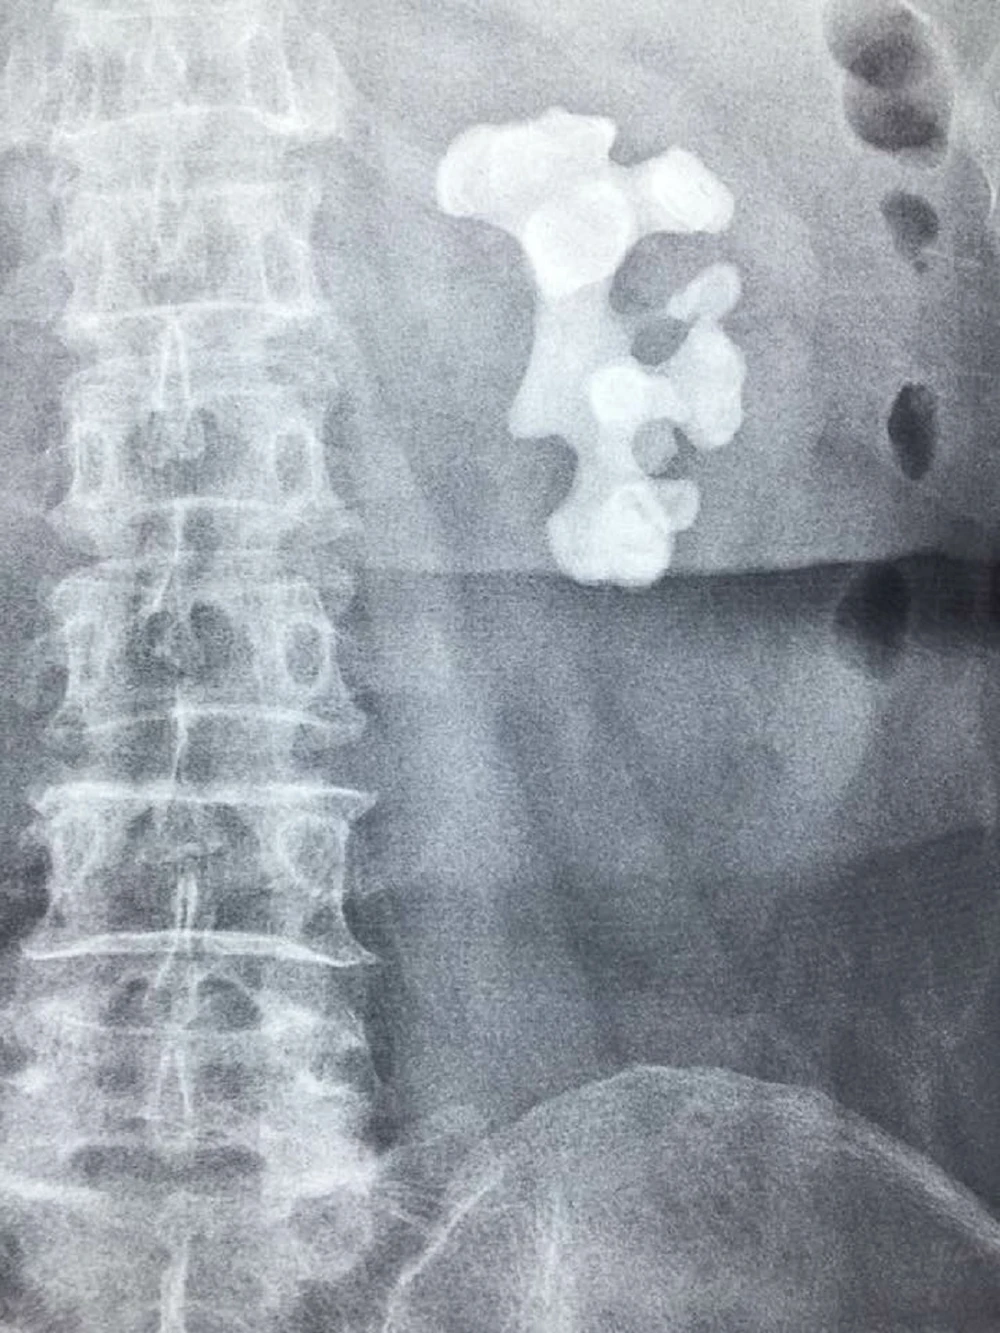

Người bệnh cảm thấy rất sợ và chần chừ điều trị. Khi đến BV ĐH Y Dược, sau khi thăm khám và chụp CT - scan, các bác sĩ khoa Tiết niệu phát hiện người bệnh bị sỏi san hô kích thước 74 mm x 48 mm, chiếm hết toàn bộ thận và các đài thận. Đây là một trường hợp sỏi thận phức tạp, hiếm gặp.

Hình CT sỏi san hô trong thận bệnh nhân. Ảnh: HP